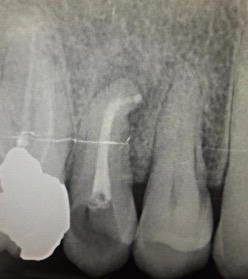

Una corretta terapia canalare con un perfetto sigillo a livello degli apici delle radici è fondamentale. I denti devitalizzati impropriamente possono creare ulteriori problemi che poi andranno a ripercuotersi sulle cure effettuate successivamente come le ricostruzioni e le corone protesiche con conseguente fallimento del piano terapeutico.

Capita spesso di incontrare denti già devitalizzati in maniera impropria che necessitano, seppur asintomatici, di essere ritrattati per evitare che i granulomi infetti visibili radiograficamente si evolvano riassorbendo tutto l’osso sottostante.